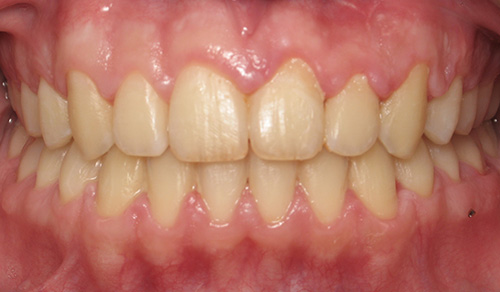

Smile Gallery

Orthodontic Treatment X-ray - Before

After Series of Teeth Extractions, Upper Left Canine Unerupted.

Ready to Start Ortho Treatment